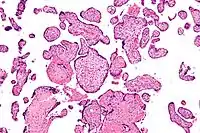

Micrografía de vilitis de etiología desconocida. Tinción H&E.

Histomorfológicamente, la VUE se caracteriza por un infiltrado linfocitario de las vellosidades coriónicas sin una causa demostrable. Las células plasmáticas deben estar ausentes; la presencia de células plasmáticas sugiere una etiología infecciosa, por ejemplo, infección por CMV